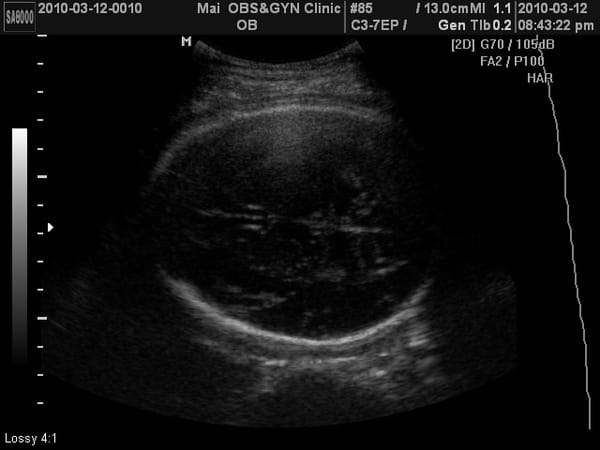

已經照不到4d了,看看小老虎的大腿骨吧~

小老虎上次產檢2050公克,這次2500公克,果然到了最後階段胎兒是以爆量在增長的。